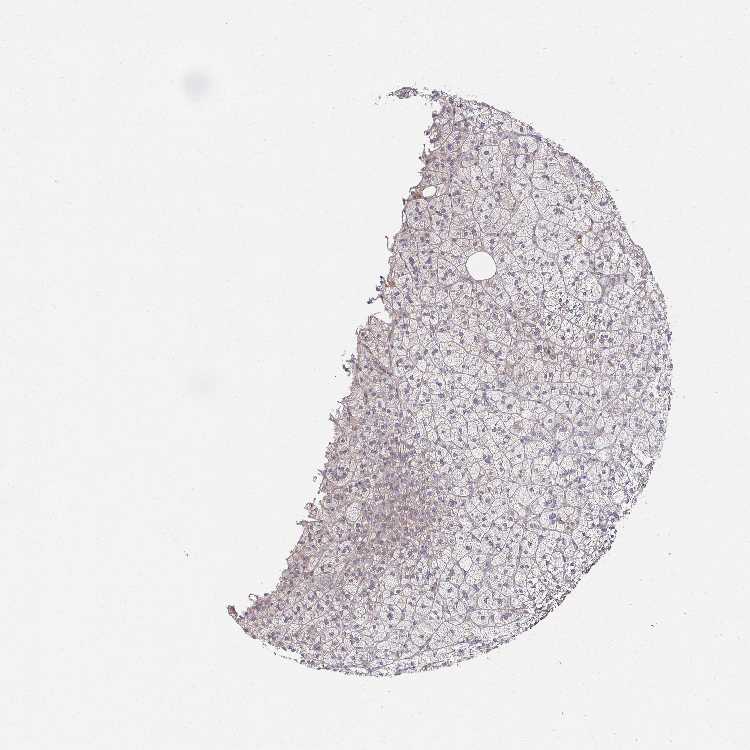

ADRENAL GLAND - Antibody stainingi

Antibody staining in the annotated cell types in the current human tissue is reported as not detected, low, medium, or high, based on conventional immunohistochemistry profiling in selected tissues. This score is based on the combination of the staining intensity and fraction of stained cells.

Each image is clickable and will lead to virtual microscopy that enables deeper exploration of all samples and also displays staining intensity scores, fraction scores and subcellular localization as well as patient and tissue information for each sample.

Antibody HPA060897

Glandular cells Low